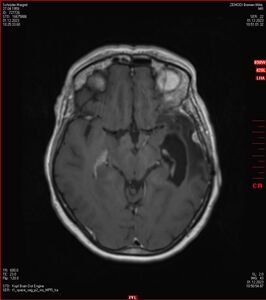

Zum Vergleich nun auch die Bilder vom 1.12.2023:

Ich denke, in den letzen 12 Monaten sind da ein paar Rezidive gewachsen,  vor 12 Monaten waren sie auch schon zu erkennen - vorher noch nicht. Nun hoffe ich auf den Rat des Spezialisten. Hoffendlich kann man etwas machen.